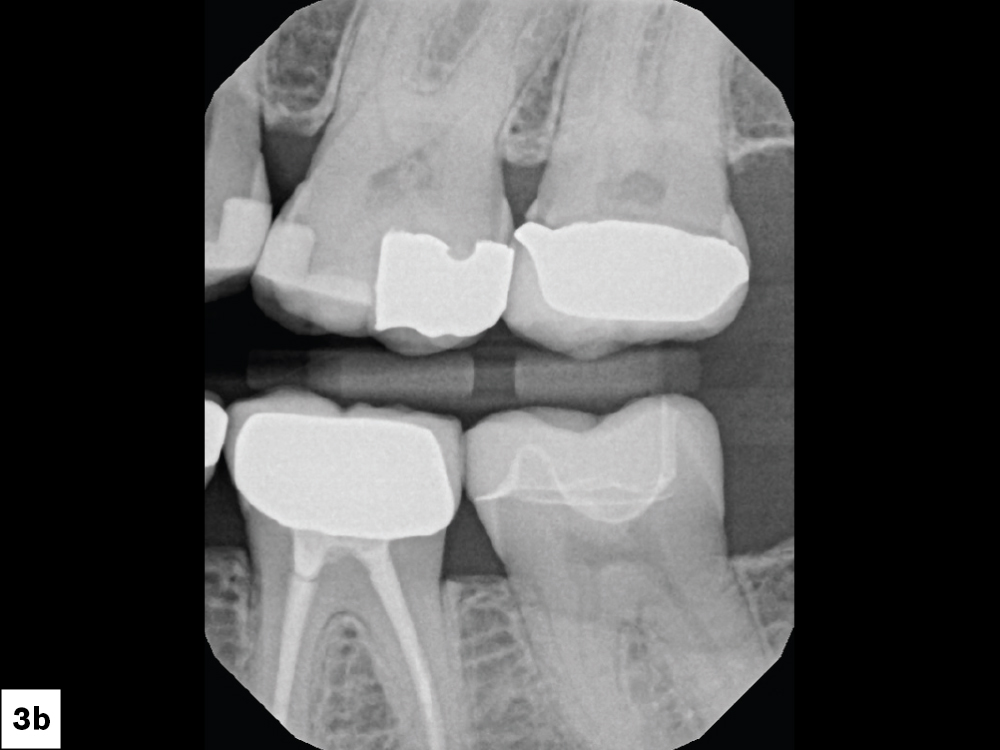

the treatment plan called for restoration of the tooth

Radiographs verified the open margin

Figures 3a, 3b: Radiographs verified the open margin, and the treatment plan called for restoration of the tooth with a same-day BruxZir® Esthetic NOW Posterior crown.